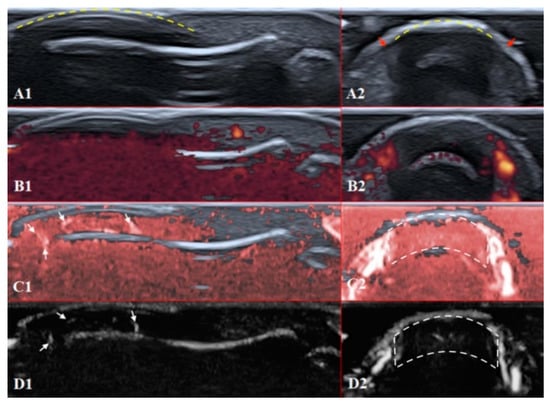

PD and SMI settings have to be standardised for all evaluations. There is an appropriate option to differentiate primary Raynaud’s syndrome from its secondary development by setting the gain. Martinoli et al. suggested increasing the gain maximally and then slowly lowering it until the noise disappears and true signals remain [20]. Rubin offered a converse way to raise the gain manually until the colour box becomes filled with signals and a true flow is distinguished from the background as the next highest signal [21]. The method by Rubin seems to be a quick and comfortable technique to check vascularity in fingertip pulp and nailfold zones (Figure 6 and Figure 7). It takes less time to evaluate vascularity by SMI modes rather than the conventional PD technique due to its higher sensitivity for low flow. Monochrome SMI is a comfortable mode for the evaluation of vasculature and even vascular torsions, as the true flow has more power, and it is easier to separate these dots from the background of random noise artefacts (Figure 4D2).

The difference between healthy and SSc-affected fingertips is obvious using Rubin’s method. Higher gain shows that there is no signal in PD and minimal dots with both SMI modes (Figure 5).

Figure 5. Ultrasound images of the nailfold of the fifth finger of the patient with a late course of SSc: (A1,A2) B mode/grayscale; yellow dotted lines mark the nail, red arrows mark the lateral nailfold, which is decreased due to sclerodactyly. (B1,B2) PD; there is an avascular zone in B2 in the deeper layers of the nailfold; B1 does not show any vascular sign with maximal gain. (C1,C2) cSMI; white arrows mark the true flow in the random noise background; the area marked by dotted lines in C2 is also avascular and the true flow signals on the sides show the lateral nailfold. (D1,D2) mSMI; confirms cSMI findings.